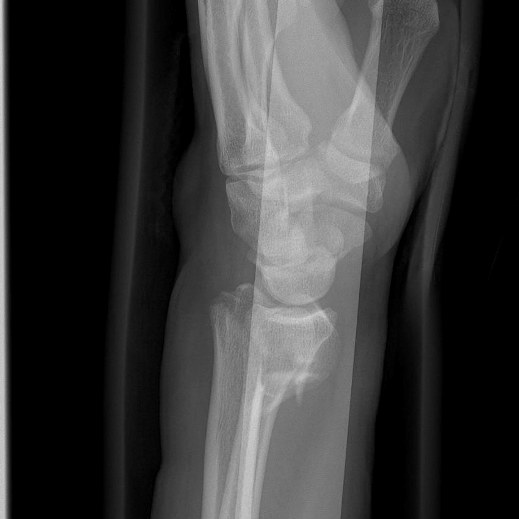

Dopo un normale e rapido stop durante la gara, tornavamo tra le ammiraglie quando c’è stata una frenata improvvisa, un corridore che mi ha precedeva non ha visto ed è caduto proprio davanti a me a 60 kmh… La conseguenza per me è una tripla frattura del radio, una frattura scomposta dello scafoide e una frattura dell’ulna… Inutile dire quanto sono demoralizzato, ancora una volta userò tutte le mie energie per tornare più forte di prima…